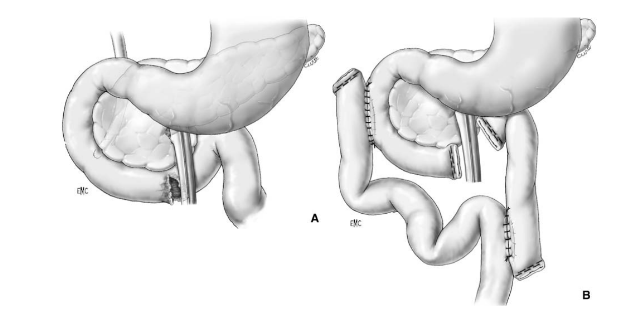

Phẫu thuật Patch tá tràng – Patch technique

A – Tổn thương rộng ở D2, lộ bóng Vater

B – Đưa quai hỗng tràng lên úp vào vết thương D2 kiểu Roux-en-Y

Phẫu thuật cắt bỏ một phần tá tràng

A- Vỡ D3 độ III (AAST) ngay sát bó mạch mạc treo tràng trên

B- Cắt đoạn D4, nối hỗng tràng với D2 Roux-en-Y